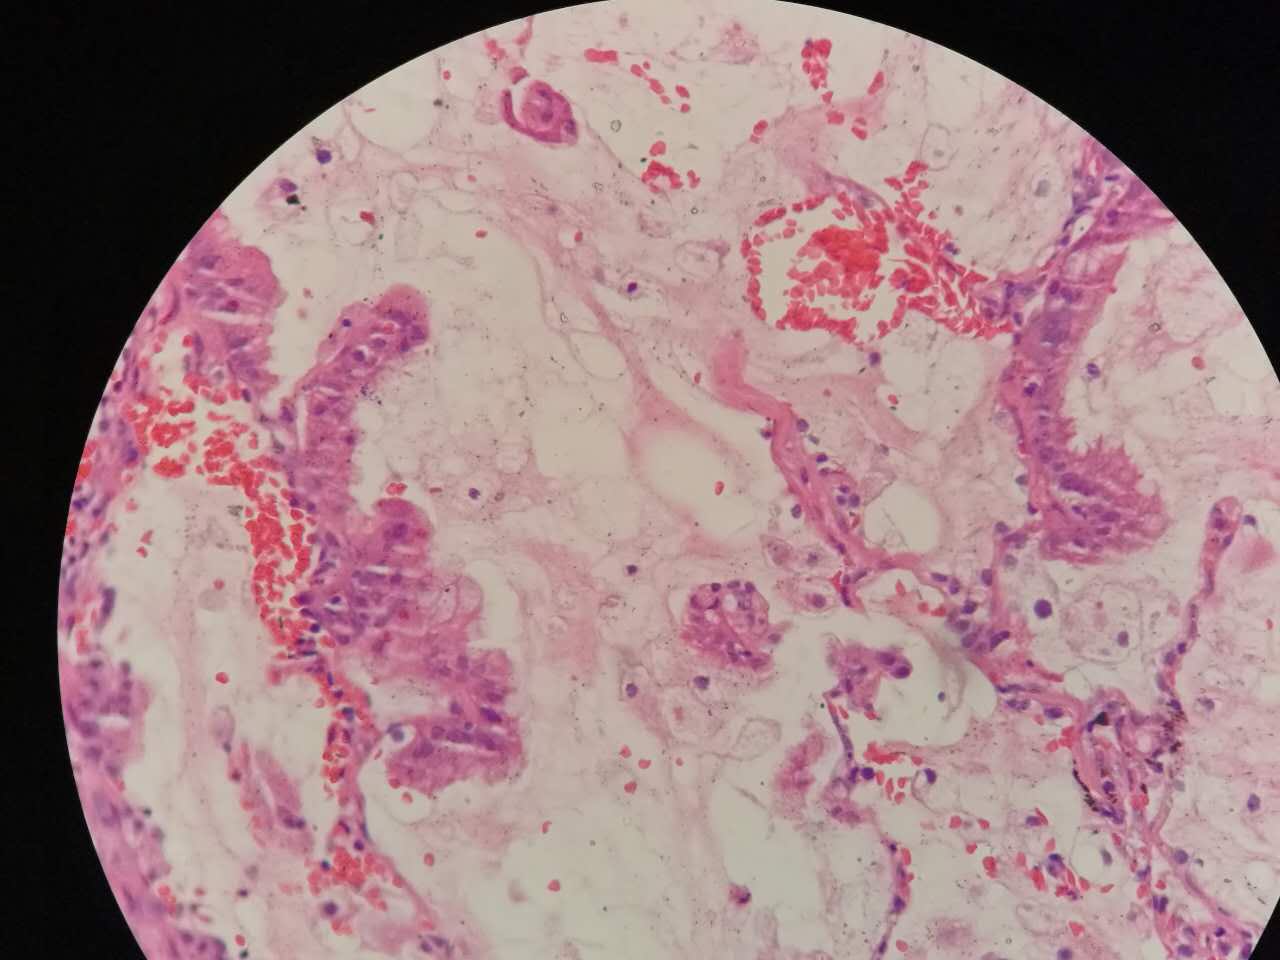

细胞外粘液湖

细胞外粘液是白色偏微红

这一幅的上方都是黏液湖

下方是正常肺泡

细胞内白颜色区是粘液,细胞外洋流样的也是粘液(湖)

黏液湖里可以飘着一些细胞,吞噬细胞及肿瘤细胞。

肿瘤细胞飘出去可以种植于肺泡上。

肿瘤细胞堆经常是离开的

中间这一团,整个都是飘过来种植长成这样

这在进展后期特别多见

早期飘散常很近